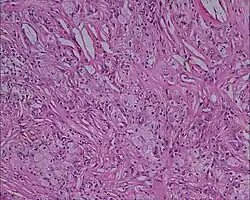

Histologie (Microscopie)

- Infiltrat dermique d'histiocytes géants parfois polynucléés (cellules de Touton) dont le cytoplasme spumeux est chargé de lipides : cholestérol essentiellement